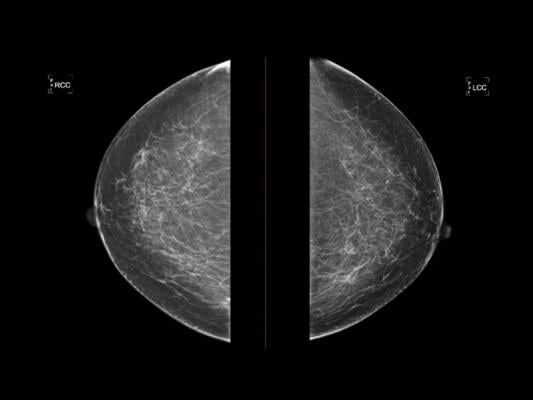

“Higher density breast tissue on mammograms means higher risk for breast cancer,” says Dr. Susan Holley, clinical director of Onsite Women’s Health and presenter of the abstract. “Therefore, breast density is an important variable to get right. We wanted to know if an AI tool could help us be right more often, over the long-term.”